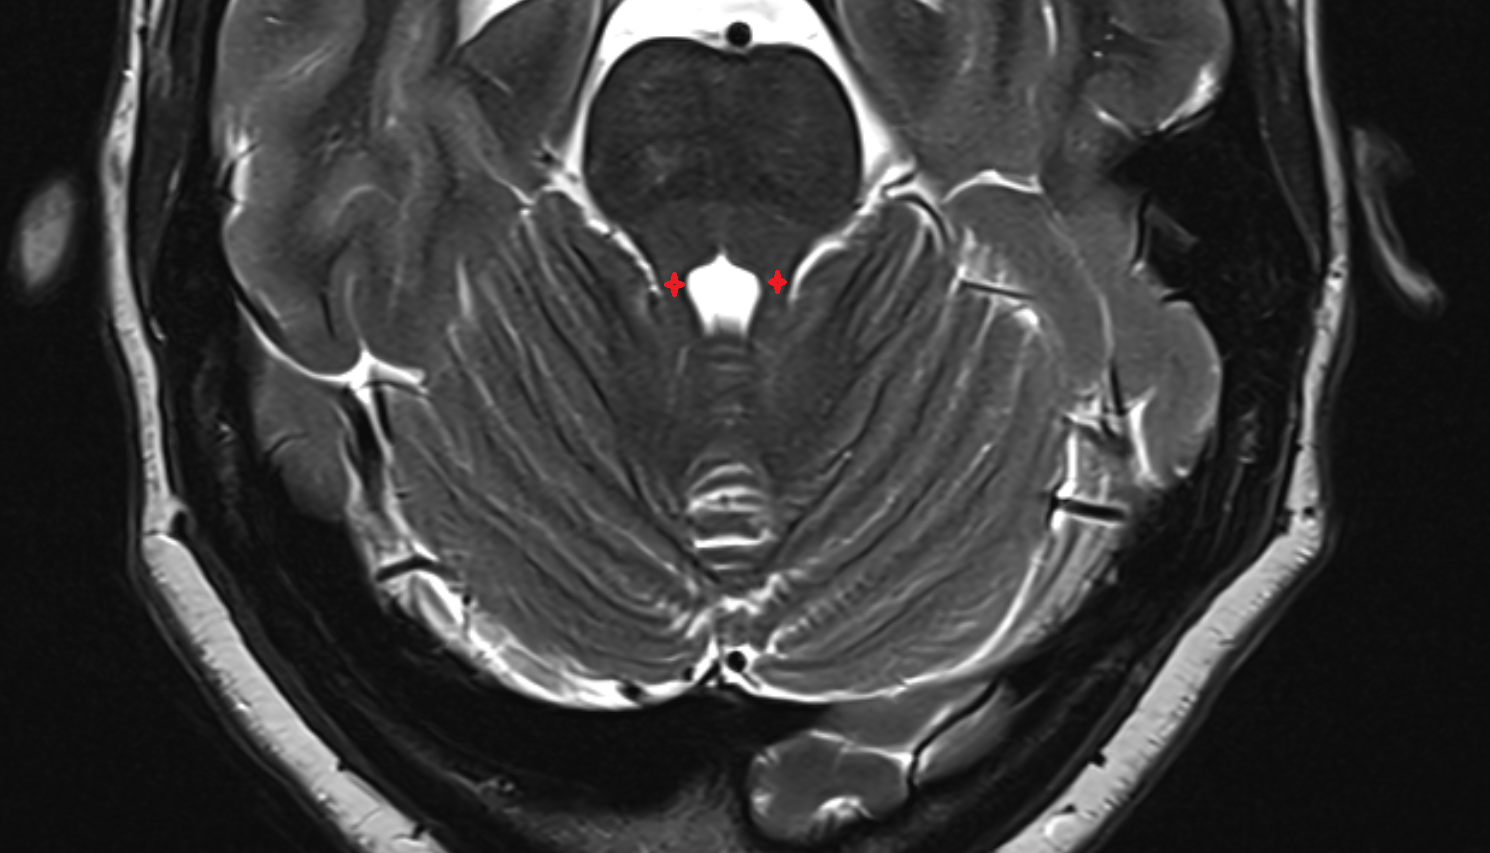

- Dentate nucleus